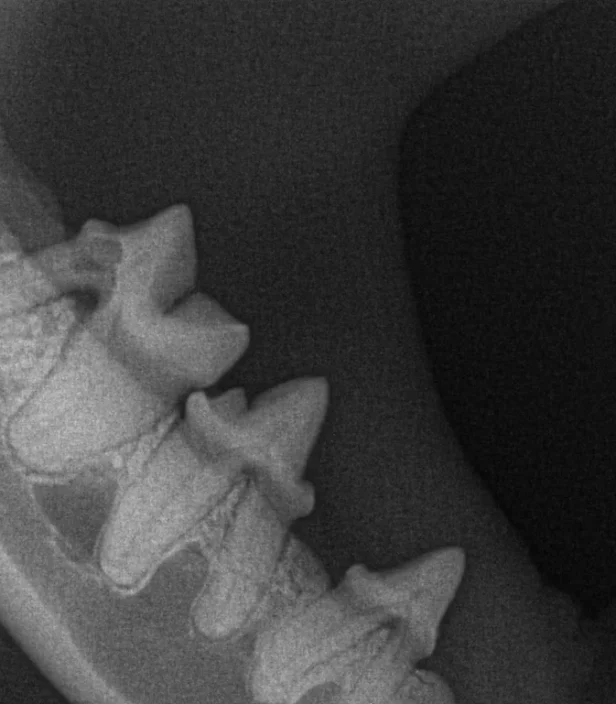

Dental radiographs are one of the most important diagnostic tools available to a veterinary dentist. They allow the internal anatomy of the teeth, the roots and the bone that surrounds the roots to be examined.

Intra-oral radiographs are made using small radiographic films or digital sensors placed inside the patient’s mouth, and provide superior quality for examination of individual teeth or sections of the jaws compared with standard-sized veterinary radiographs. Because veterinary patients will not cooperate when a radiograph or sensor is placed in the mouth, taking dental radiographs requires that the patient is anaesthetised or sedated.